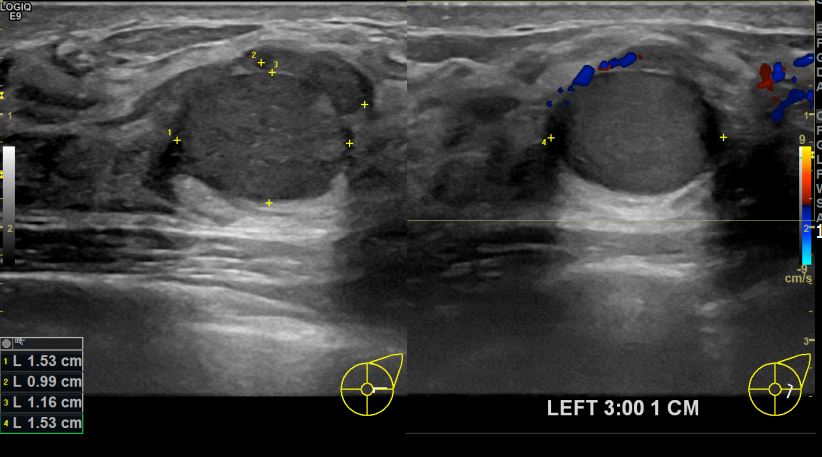

아산유외과개원후 712번째 유방암진단

상기환자 건진상 이상소견으로 조직검사권유받고 내원하신 40대 여성분으로 좌측유방멍울 조직검사시행후 유방암 진단되었습니다